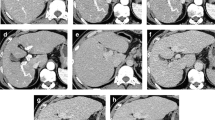

Our institutional review board approved this prospective study. Written informed consent was obtained from all patients. Twenty-eight consecutive patients with PDAC undergoing chemotherapy (14 men and 14 women; mean age, 68.4 years) underwent pancreatic LDCT for therapy evaluation. The LDCT images were reconstructed using 40% adaptive statistical iterative reconstruction-Veo (hybrid-IR) and DLIR at medium and high levels (DLIR-M and DLIR-H). The image noise, diagnostic acceptability, and conspicuity of PDAC were qualitatively assessed using a 5-point scale. CT numbers of the abdominal aorta, portal vein, pancreas, PDAC, background noise, signal-to-noise ratio (SNR) of the anatomical structures, and tumor-to-pancreas contrast-to-noise ratio (CNR) were calculated. Qualitative and quantitative parameters were compared between the hybrid-IR, DLIR-M, and DLIR-H images.

CT dose-index volumes and dose-length product in pancreatic LDCT were 2.3 ± 1.0 mGy and 74.9 ± 37.0 mGy•cm, respectively. The image noise, diagnostic acceptability, and conspicuity of PDAC were significantly better in DLIR-H than those in hybrid-IR and DLIR-M (all P < 0.001). The background noise was significantly lower in the DLIR-H images (P < 0.001) and resulted in improved SNRs (P < 0.001) and CNR (P < 0.001) compared with those in the hybrid-IR and DLIR-M images.

DLIR significantly reduced image noise and improved image quality in pancreatic LDCT images compared with hybrid-IR.